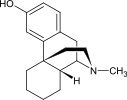

The pharmacodynamic response to an opioid depends upon the receptor to which it binds, its affinity for that receptor, and whether the opioid is an agonist or an antagonist. For example, the supraspinal analgesic properties of the opioid agonist morphine are mediated by activation of the μ1 receptor; respiratory depression and physical dependence by the μ2 receptor; and sedation and spinal analgesia by the κ receptor. Each group of opioid receptors elicits a distinct set of neurological responses, with the receptor subtypes (such as μ1 and μ2 for example) providing even more [measurably] specific responses. Unique to each opioid is its distinct binding affinity to the various classes of opioid receptors (e.g. the μ, κ, and δ opioid receptors are activated at different magnitudes according to the specific receptor binding affinities of the opioid). For example, the opiate alkaloid morphine exhibits high-affinity binding to the μ-opioid receptor, while ketazocine exhibits high affinity to ĸ receptors. It is this combinatorial mechanism that allows for such a wide class of opioids and molecular designs to exist, each with its own unique effect profile. Their individual molecular structure is also responsible for their different duration of action, whereby metabolic breakdown (such as N-dealkylation) is responsible for opioid metabolism.

The first fully synthetic opioid was meperidine (later demerol), found serendipitously by German chemist Otto Eisleb (or Eislib) at IG Farben in 1932.[228] Meperidine was the first opiate to have a structure unrelated to morphine, but with opiate-like properties.[199] Its analgesic effects were discovered by Otto Schaumann in 1939.[228] Gustav Ehrhart and Max Bockmühl, also at IG Farben, built on the work of Eisleb and Schaumann. They developed "Hoechst 10820" (later methadone) around 1937.[230] In 1959 the Belgian physician Paul Janssen developed fentanyl, a synthetic drug with 30 to 50 times the potency of heroin.[211][231] Nearly 150 synthetic opioids are now known.[228]

- Fully synthetic opioids: such as fentanyl, pethidine, levorphanol, methadone, tramadol, tapentadol, and dextropropoxyphene;